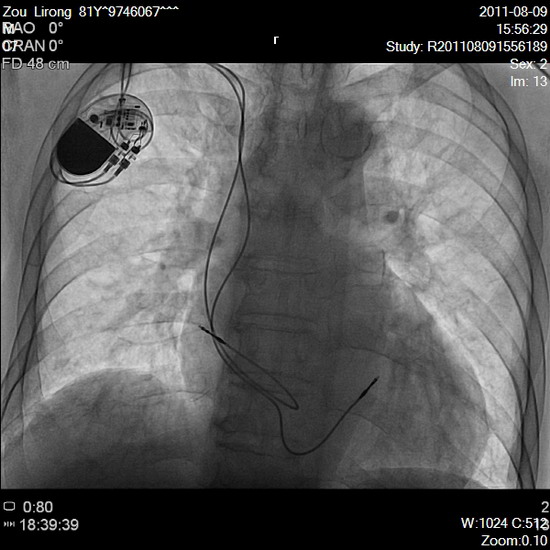

老人今年81岁,经常无故出现气短,乏力,头晕眼花,甚至晕厥,每次犯病患者和家属都极度恐慌,为求医来我院心内科就诊。经全面检查,明确诊断为“病窦综合征”,发病时出现心脏停搏,心率仅20-30次/ 分,非常危险,随时可能猝死,唯一解决的办法就是安装心脏永久起搏器。考虑病人高龄,合并有心、肾功能下降,黄汝刚主任建议请上级医院专家来完成手术,家属却坚定地说:“主任,我们谁也不请,就相信你,手术就你来做。”带着患者的信任,凭借以往请专家的十几例安装经验,经过按部就班的准备,顶着首次“扔开拐棍”的压力,手术在导管室如期进行。消毒,铺单,局部麻醉,手术开始,但老人却十分不配合,一会儿嫌憋得慌,一会儿觉得躺的难受,在狭窄的导管床上来回翻动,还要起来上厕所……。医护人员一边安慰病人,一边实行无菌保护措施,还要在射线下继续手术,难度可想而知。而心电监护仪上的数字一会儿正常,一会儿出现心脏停搏,频繁地变换让所有人的心都提到了嗓子眼。此时药物的支持作用已微乎其微,手术的成功与否,直接决定了病人的生与死,在这种情况下,黄主任虽然是第一次独立做这样的手术,仍然保持镇定自若,全神贯注地进行每一步操作,锁骨下静脉穿刺,置入鞘管,将心室电极、心房电极分别送入心脏恰当位置,测试参数,将起搏器调整到最适合病人的起搏状态,开始起搏!监护仪显示规律的起搏信号,心脏跟着有节律的跳动,手术成功了,导管室内每个人都用凝重而喜悦的眼神相互传递着那份来之不易、超越自我的幸福。

还记得十一长假,一位平素健康的48岁男性农民,突然晕厥,急来院查心电图为Ⅲ度房室传导阻滞,心率30次/分,生命危在旦夕。正在家中休息的黄主任立即来院,在导管室为患者安装了心脏临时起搏器,首先保证了病人的生命安全,再进一步查找原因,调整药物,期望能恢复其自身心律。一周后,病人心律奇迹般恢复,但为防止病情复发,黄主任还是独立为其安装了永久起搏器,手术非常成功,病人很快痊愈出院。

相关链接:人体各脏器的生理功能,必须靠心脏维持适当频率的节律舒缩,保证所需新鲜血液的供应才能完成。正常心脏收缩的频率为60-100次/分,若心率过低,排血量将必受影响。安装心脏起搏器就是将一个小巧的精密仪器通过一个细致的手术装入体内,可使过缓的心率提高到所需的频率,从而保证心脏正常的排血量以供脏器的需要。一般情况下,实施该手术只需1个小时左右。

心脏起搏器(cardiac pacemaker),就是一个人为的“司令部”,它能替代心脏的起搏点,使心脏有节律地跳动起来。心脏起搏器是由电池和电路组成的脉冲发生器,能定时发放一定频率的脉冲电流,通过起搏电极导线传输到心房或心室肌,使局部的心肌细胞受到刺激而兴奋,兴奋通过细胞间的传导扩散传布,导致整个心房和(或)心室的收缩。心脏的电信号使它跳动。当运行时,心脏跳动加速;当睡眠时,心脏跳动减慢。如果心电系统异常,心脏跳得很慢,甚至可能完全停止。人工心脏起膊器发出有规律的电脉冲,能使心脏保持跳动。